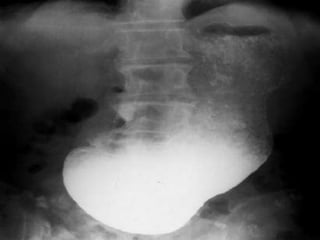

Chụp X quang dạ dày cản quang:

 Dạ dày dãn to

 Hình 3 tầng

 Thuốc không thoát qua

tá tràng

Albumin giảm,Bun,Cre tặng Ion đồ giảm: Cl,Na,Ka,Ca Chụp X quang dạ dày cản quang:  Dạ dày dãn to  Hình 3 tầng  Thuốc không thoát qua tá tràng  Phần hang vị hai bờ vẫn mềm mại(do loét) hay có hình lõi táo (do ung thư hang vị)

Chiếu X-quang: -Hình ảnhtuyết rơi -Sóng nhu động tăng nhanh và mạnh trong giai đoạn tăng trương lực và ngược lại *Lưu ý trước khi chụp phải khám kĩ bệnh nhân để loại trừ thủng tạng và tắc ruột